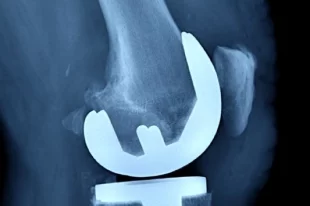

Титулованному самбисту Кочугову провели операцию в Нижнем Новгороде

Врачи считают, что после реабилитации Вячеслав Кочугов сможет вернуться в профессиональный спорт.